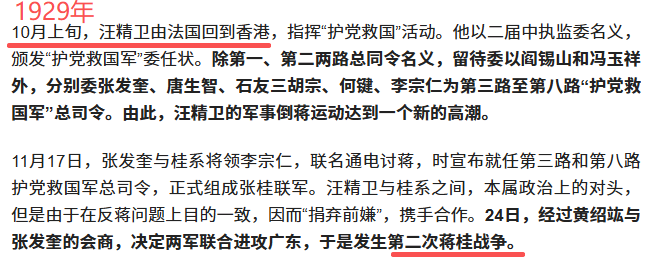

1929年10月汪精卫才从法国回香港,中医骗那是张嘴就谎啊,还张嘴就汪精卫掌实权,汪精卫1929年10月回来是支持第二次蒋桂战争干老蒋的,他还掌实权。 中医骗的特点就是张嘴就喷谎。主打一个我虽然小学3年级文化,但是够我骗文盲。 1929年,弗莱明刚刚发明抗生素,还只是实验室与论文,这就跑中国来了? 1929年,面对细菌性痢疾,西医就是没有办法治疗,所以就说治不了。1929年弗莱明虽然已经发明青霉素,但是产量感人,当时第一次使用对一个受伤感染的警察,非常有效,但是手中的一点青霉素用完了,于是警察还是shi了。 所以,西医诚实的说,没有办法治疗。 而诚实,是一种多么宝贵的品质。 因为你诚实,你说出来:我不能治疗,那么,这个疾病,就有了解决了一半。 因为你以后,所有的西医,西药,医疗器械从业者,都会想尽办法去攻克这个疾病。 而多少的绝症,曾经的绝症,因为西医的诚实,而最终研究出了真正治疗办法。 例如1921年的胰岛素。 例如1929年的青霉素。 例如1998年的伟哥。 例如2006年的HPV疫苗。 你没有。 3、西医不仅是个自然科学,他还是个管理秩序。 没有人敢保证每个西医从业者都会履行自己的诺言,所以西医除了希波克拉底誓言,还双管齐下,有一套完整的制度。 1)、一人为私,二人为公。西医的任何重大治疗与决策都是多人完成。 手术有术前评估,有术前讨论。 化验师管理体系是单独的。检查技师管理体系是单独的。甚至护士也是单独独立的。护士只是执行医生的医嘱,只是工作关系,不是上下级。护士的管理也是独立的,不归医生管理。麻醉师的管理也是独立的。 而这么多的独立,就是垂直管理,在根子上就切断医生自己一手遮天的可能。 2)、完善的文档记录。 住院病例保存30年。 住院病例需要上级医生签名。需要三级签名。修改需要红笔。 交病案后就归病案室,医生是要不回来了的。因为病案室也是独立的。 出院一定会给出院小结。需要全病历的也可以,掏复印费去病案室复印,所有的医院都允许。 所以很多中医骗张嘴就是他啥病西医看不好去找中医一看就好了,我就让他发出院小结,结果没有一个发的。我不要你隐私,你把你个人隐私涂掉,我就要病案。没有,全闪了。 等等。 在网上随便找点: |

一份最简单的住院小结,而且是格式化的,入诊、出诊、入情、治经、出情、医嘱,是格式化的,医生根本就删不掉。 送礼物 还没有人送礼物,鼓励一下作者吧 |